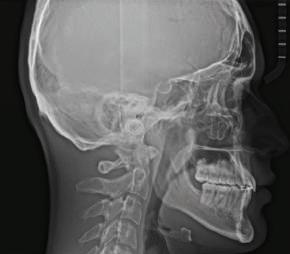

Dental Tribune Bulgarian Edition / октомври 2022 г. 17клиничен случай с алайнери леко струпване в долната че люст; несъответствие по Болтън (мандибуларен излишък от 3.06 мм във фронталната зона и общо 1.47 мм); издължено лице с лицева аси метрия; конвексен профил с ретруди рана долна челюст и проми нентен нос. На мястото на зъб #46 бе на лице имплант, а зъби #16 и 26 са ендодонтски лекувани. Тези зъби бяха асимптоматич ни, затова бе взето решение да се прави релечение само при нужда. Мъдреците липсваха. Анализът на телерентгеногра фията (фиг. 4) показа ретрог натна мандибула (SNB: 74.2°) и нормална инклинация на резците както в

Цели на лечението и лечебен план Целите на лечението бяха следните: нивелиране и подреждане на зъбите и в двете зъбни дъги; отваряне на пространство за липсващия латерален резец; коригиране на отношенията при канините и моларите до клас I; и корекция на отклонението на срединната линия. Лечебният план включваше: корекция на отношенията при кучешките зъби и мола рите до клас I с дистализира не на максилата; отваряне на пространство в областта на #22 за поставя не на единичен имплант; корекция на срединната ли ния; и създаване на място за раз ширяване на зъб #12 и апрок симална редукция в долната челюст с цел подобряване на несъответствието по Болтън и осигуряване на подобра оклузия. Изпълнение на лечебния план Този случай бе изпълнен със системата за алайнери Invisalign (Align Technology). Одобреният първоначален лечебен план предвиждаше 49 алайне ра с дистализиране на задни те горни зъби до клас I (прибли зително с около 3.5 мм; фиг. 5). За бъдещия имплант в областта на липсващия латерал бе планирано пространство от 6.5 мм, докато във фронталния сегмент на долната челюст бе предвидена апроксимална редук ция. В дясната страна бутон за ластици клас II бе поставен на зъб #47 вместо на зъб #46, за да не се увреди короната на импланта. Понеже пациентката жи вееше в чужбина,

Що се отнася до финалния це фалометричен анализ, лице вата височина

(LFH: 56.5 mm) и размерите на меките тъка ни останаха непроменени. На клонът на горните резци бе за пазен (Ui–FH: 115.8°), а долните резци бяха леко наклонени ве стибуларно (Li–APog: 30°; фиг. 16). ДИСКУСИЯ Липсата на зародиш на по стоянен горен латерален резец е налице при 3.5–6.5% от евро пеидната раса, като при жени е по-честа, отколкото при мъ жете в съотношение 3:2.8–10 Възможни са няколко лечебни подхода, включително замя ната му с преоформен канин, отваряне на място чрез орто донтско лечение и протетич но възстановяване, както и ав тотрансплантация. Устано вено е, че изборът за затваря не на място или за отваряне то му все още подлежи на дис кусия сред ортодонти и проте зисти.11,12 Според литературните дан ни затварянето на простран ството и замяната на липсва щия латерал с канин се предпо чита в случаи на едностранна липса на зародиш, балансиран профил, кучешки зъби и премола ри със сходна форма и цвят, дву челюстна протрузия или клас II малоклузия.13–15 Отваряне на пространство по-често се изби ра при клас I, наличие на диасте ми и треми в горната зъбна дъга или голяма разлика в размерите на канини и премолари.16 Скорошно проучване е уста новило, че изборът на лечение при конгенитално липсващ ла терал е пряко свързан със след ните фактори17: възрастта на пациента при започване на лечението; индивидуалните особености при всеки конкретен случай; и сътрудничеството между специалистите в лекуващия екип. Макар да има проучвания, фа воритизиращи леченията със затваряне на място11,18, всеки случай трябва да бъде оценяван индивидуално. В презентирания в тази статия случай бе взето решение за отваряне на мяс то и протетично възстановя ване, понеже целта бе да се по стигнат клас I отношения при канините и моларите, както и по-широка усмивка. За да се из бегнат компромиси, след лече нието бе постигнат клас I при моларите и кучешките зъби, несъответствието по Болтън бе подобрено и срединната ли ния бе коригирана. Други изслед вания демонстрират отлични естетични и функционални ре зултати при лечение с отваря не на място и протетична ре хабилитация.19 И двете лечеб ни модалности са подходящи за третиране на вродена лип са на зародиш на латерал и да ват сходни функционални и па родонтални резултати20, като при едно проучване

ти и клас II ластици е устано вено, че осигурява достатъч на дистализация без промяна на лицевата височина.23 Както се видя от цефалометричния анализ, точно това бе постиг нато и в представения случай като се има предвид, че лице вата височина остана същата като първоначалната. Предвид леката тенденция към дистал Фиг. 8a–e Поръчаните допълнителни алайнери. Фиг. 9 Панорамна рентгенография след края на лечението. Фиг. 10a–c Странични (а и с) и фронтална интраорални снимки след края на ортодонтското лечение и поставянето на импланта (b). Зъб #12 все още не беше протезиран. Фиг. 11а и b Оклузални снимки след ортодонтското лечение. Фиг. 7a Фиг. 8a Фиг. 7d Фиг. 8d Фиг. 9 Фиг. 10a Фиг. 10b Фиг. 10c Фиг. 11bФиг. 11a Фиг. 7b Фиг. 8b Фиг. 7e Фиг. 8e Фиг. 7c Фиг. 8c Фиг. 7a–e Интраоралната ситуация по време на лечението. клиничен случай с алайнери